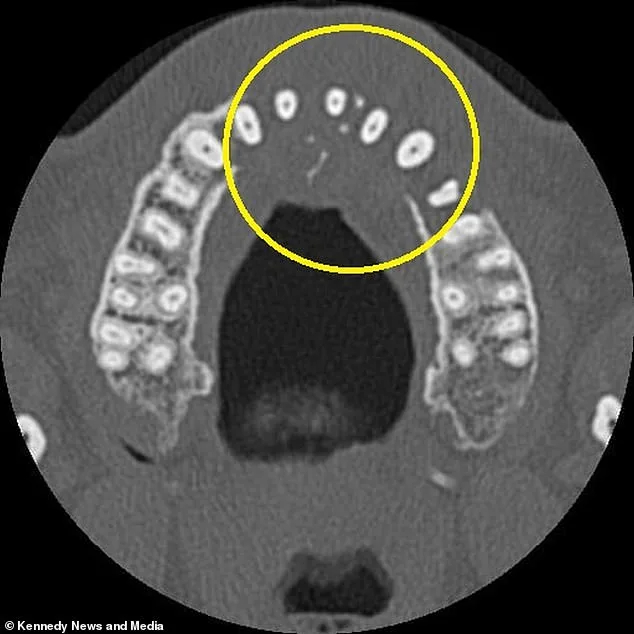

A 42-year-old man from Northamptonshire is warning others not to dismiss even minor tooth pain after discovering it was a symptom of an aggressive blood cancer. Edd Vieira, who was vacationing in Portugal in August 2025, first noticed a dull ache in his left canine. He assumed it was a simple cavity and planned to seek a filling. Within days, however, his front and left teeth began aching and loosening, prompting him to visit a local dentist. The routine X-ray revealed an alarming absence of bone in the left side of his upper jaw. A subsequent CT scan uncovered a mass in his sinus cavity, spreading beneath his nose. The diagnosis came as a shock: stage two diffuse large B-cell lymphoma (DLBCL), a fast-growing form of non-Hodgkin lymphoma that affects white blood cells.

The cancer had already begun to erode his upper jawbone and had started spreading to his neck. Mr. Vieira described the progression of his symptoms: the initial ache in his canine, followed by wobbling teeth, pain when blowing his nose, and the discovery of a hard lump near his nostril. His wife, Mandy Vieira, 44, expressed disbelief at the diagnosis. She said her husband had always been in excellent health, making the sudden revelation even more jarring. 'I was in shock, crying my eyes out,' she said. 'Edd stayed positive, just saying, "We'll deal with this."'